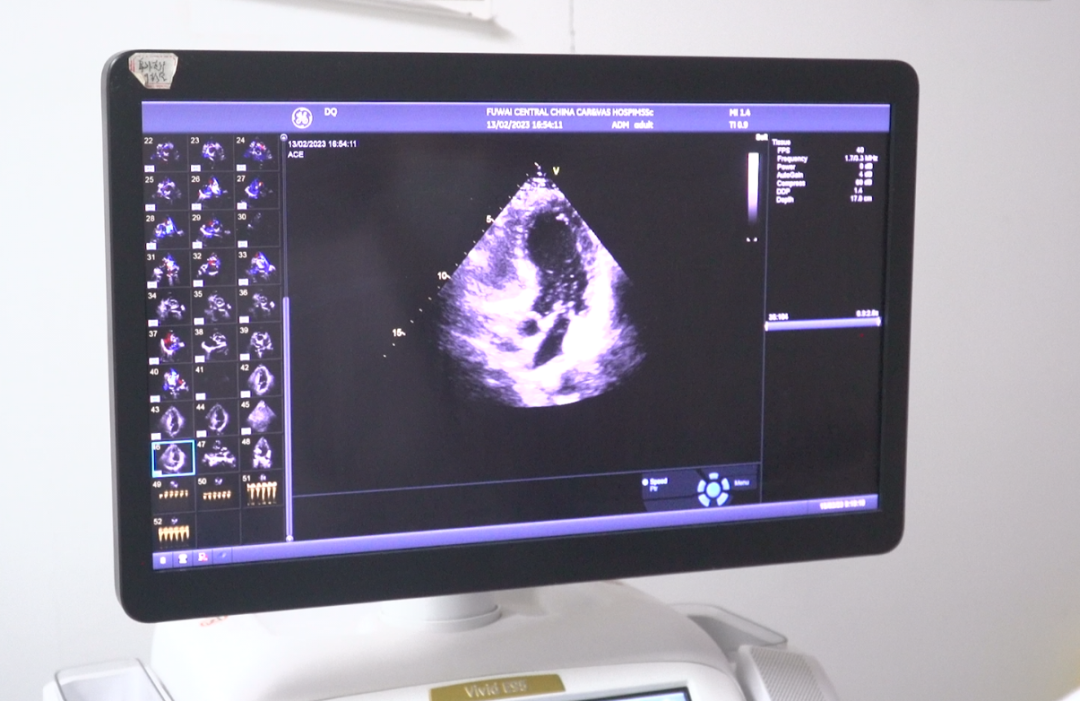

2月15日,在阜外華中心血管病醫(yī)院超聲科,田新橋主任團(tuán)隊(duì)使用右心聲學(xué)造影技術(shù)(又稱發(fā)泡實(shí)驗(yàn)),僅用幾分鐘就明確了診斷。

幾分鐘后,專家果然發(fā)現(xiàn)異常。從屏幕上可以清晰看到,患者左心房?jī)?nèi)很快出現(xiàn)了微小氣泡,這說(shuō)明該患者的心臟存在著房水平由右向左的分流,提示有先天性卵圓孔未閉!

整個(gè)右心聲學(xué)造影檢查過(guò)程約10分鐘,患者沒(méi)有任何不適癥狀。與先天性心臟卵圓孔未閉的常規(guī)檢查手段——傳統(tǒng)心臟彩超相比,右心聲學(xué)造影的敏感性和特異性更高,通過(guò)這種方法終于找出了王先生多年頭痛問(wèn)題的根源。